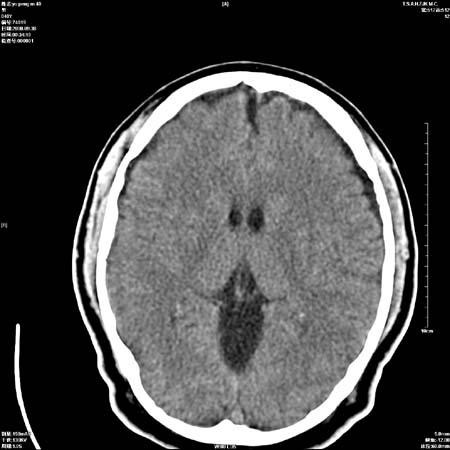

以下是引用zjzjr在2008-10-4 20:29:00的发言:[br]右颞叶皮质区密度略减低,脑沟较对侧变浅,考虑早期脑梗塞,建议mri.左侧小脑幕缘旁可见带状低密度影,轻度占位效应,支持蛛网膜囊肿,枕大池区亦考虑蛛网膜囊肿.

以下是引用流浪星在2008-10-4 20:06:00的发言:[br]大脑大静脉池增宽,脑萎缩引起,目前的ct表现不能解释临床症状,建议短期复查或做mr检查。